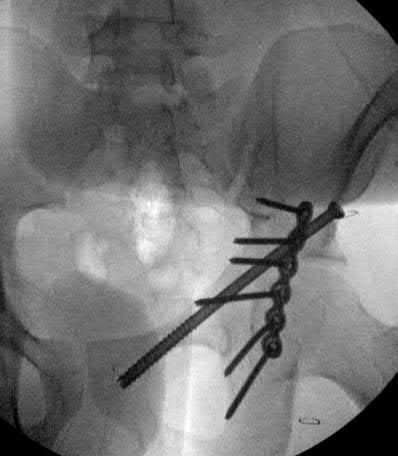

Question 1:

A 12-year-old obese boy presents with vague left thigh and knee pain. He is diagnosed with a Slipped Capital Femoral Epiphysis (SCFE) as seen in similar clinical scenarios. During percutaneous in-situ fixation, unrecognized penetration of the guide wire into the hip joint occurs. What is the most likely specific complication resulting from this technical error?

Correct Answer: Chondrolysis

Explanation:

Chondrolysis is a severe complication of SCFE characterized by rapid destruction of the articular cartilage. While it can occur idiopathically, its most established iatrogenic cause is unrecognized intra-articular hardware penetration. The 'approach-withdraw' fluoroscopic technique is required during pinning to assure pins are entirely intraosseous. Avascular necrosis (AVN) is usually due to damage to the epiphyseal blood supply (retinacular vessels) secondary to the initial displacement, forceful closed reduction, or posterosuperior pin placement.